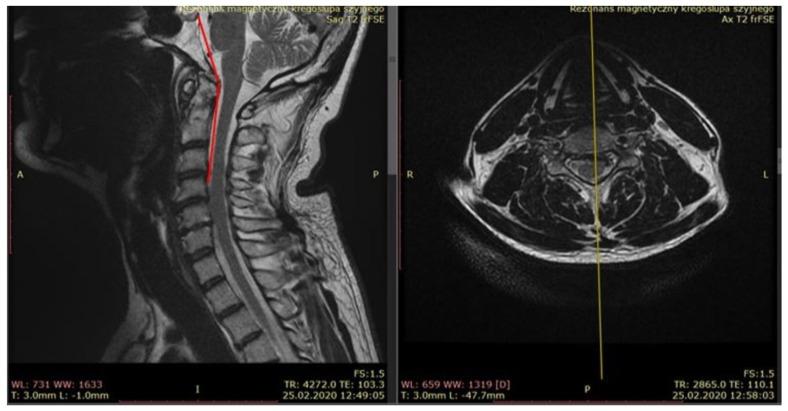

This paper presents the anatomical and biomechanical aspects of chronic instability of the craniocervical junction (CCJ) with a discussion on clinical diagnostics based on mobility tests and provocative tests related to ligamentous system injuries, as well as radiological criteria for CCJ instability. In addition to the structural instability of the CCJ, the hypothesis of its functional form resulting from cervical proprioceptive system (CPS) damage is discussed. Clinical and neurophysiological studies have shown that functional disorders or organic changes in the CPS cause symptoms similar to those of vestibular system diseases: dizziness, nystagmus, and balance disorders. The underlying cause of the functional form of CCJ instability may be the increased activity of mechanoreceptors, leading to "informational noise" which causes vestibular system disorientation. Due to the disharmony of mutual stimulation and the inhibition of impulses between the centers controlling eye movements, the cerebellum, spinal motoneurons, and the vestibular system, inadequate vestibulospinal and vestibulo-ocular reactions occur, manifesting as postural instability, dizziness, and nystagmus. The hyperactivity of craniocervical mechanoreceptors also leads to disturbances in the reflex regulation of postural muscle tone, manifesting as "general instability". Understanding this form of CCJ instability as a distinct clinical entity is important both diagnostically and therapeutically as it requires different management strategies compared to true instability. Chronic CCJ instability significantly impacts the quality of life (QOL) of affected patients, contributing to chronic pain, psychological distress, and functional impairments. Addressing both structural and functional instability is essential for improving patient outcomes and enhancing their overall QOL.

本文介绍了颅颈交界区(CCJ)慢性不稳定的解剖学和生物力学方面,并讨论了基于与韧带系统损伤相关的活动度测试和激发试验的临床诊断方法,以及CCJ不稳定的放射学标准。除了CCJ的结构不稳定外,还讨论了由颈本体感觉系统(CPS)损伤导致的其功能形式的假说。临床和神经生理学研究表明,CPS的功能障碍或器质性改变会导致与前庭系统疾病相似的症状:头晕、眼球震颤和平衡障碍。CCJ不稳定功能形式的潜在原因可能是机械感受器活动增加,导致“信息噪声”,从而引起前庭系统定向障碍。由于控制眼球运动的中枢、小脑、脊髓运动神经元和前庭系统之间相互刺激和冲动抑制的不协调,会出现不充分的前庭脊髓和前庭眼反应,表现为姿势不稳、头晕和眼球震颤。颅颈机械感受器的活动亢进还会导致姿势肌紧张反射调节紊乱,表现为“全身不稳定”。将这种形式的CCJ不稳定理解为一种独特的临床实体在诊断和治疗方面都很重要,因为与真正的不稳定相比,它需要不同的管理策略。慢性CCJ不稳定会显著影响受影响患者的生活质量(QOL),导致慢性疼痛、心理困扰和功能障碍。解决结构和功能不稳定问题对于改善患者预后和提高他们的整体生活质量至关重要。